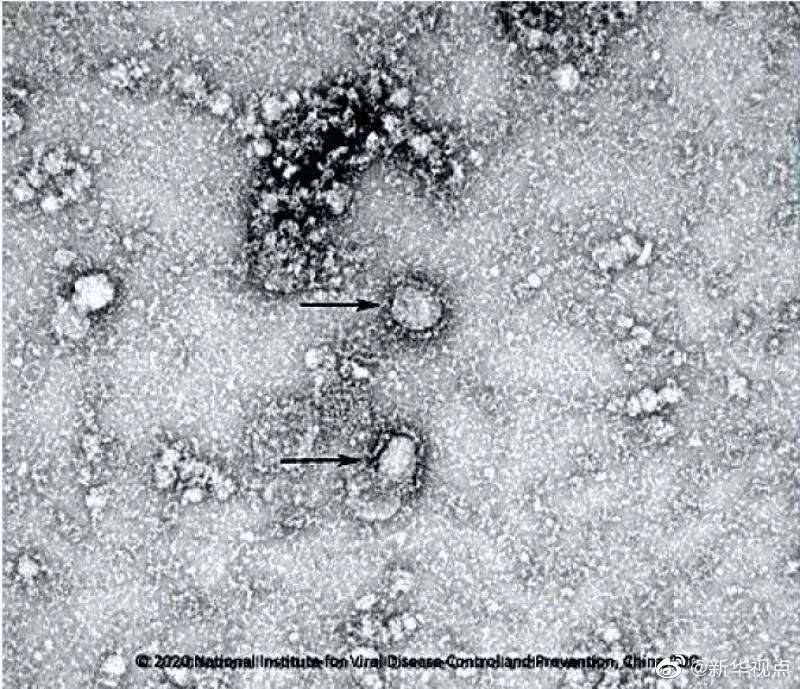

好消息!中国疾控中心成功分离我国首株新型冠状病毒毒种,它长这样!

国家病原微生物资源库于2020年1月24日发布了由中国疾病预防控制中心病毒病预防控制所成功分离的我国第一株病毒毒种信息及其电镜照片、新型冠状病毒核酸检测引物和探针序列等国内首次发布的重要权威信息,并提供共享服务。看病毒“真容”↓↓↓(记者田晓航、王秉阳)